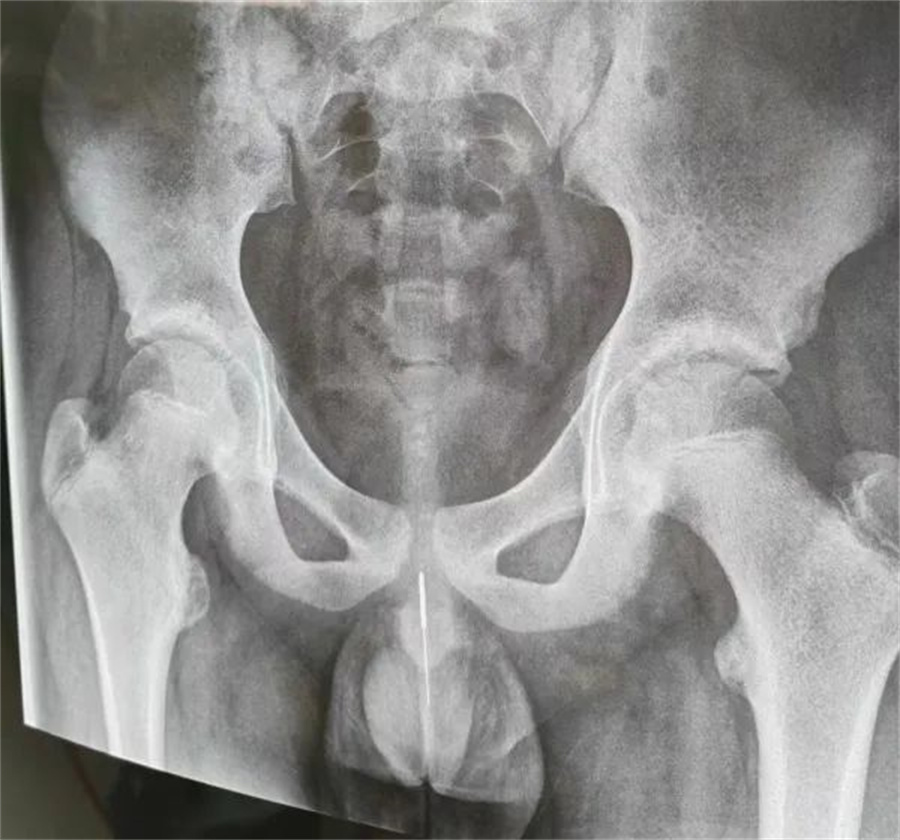

急诊外科接诊后立即收入院并第一时间做好手术准备,此时泌尿外科主任谢方达也紧急从家中赶到了医院,经过术前检查,确认银针卡在了接近球部尿道的部位,位置比较深,又没进入到膀胱里,如何尽快地取针成为一个颇具难度的挑战。

孩子家长和泌尿外科专家都希望用最微创的方式完成手术。但因孩子年龄小、尿道细,体重又偏大而难以实现,术中医生在保证对孩子造成伤害最小的前提下,采取隐匿小切口的方式,顺利将6.5cm的银针从尿道中刺破取出,为孩子解除了困扰,术后恢复三四天后即可顺利出院。